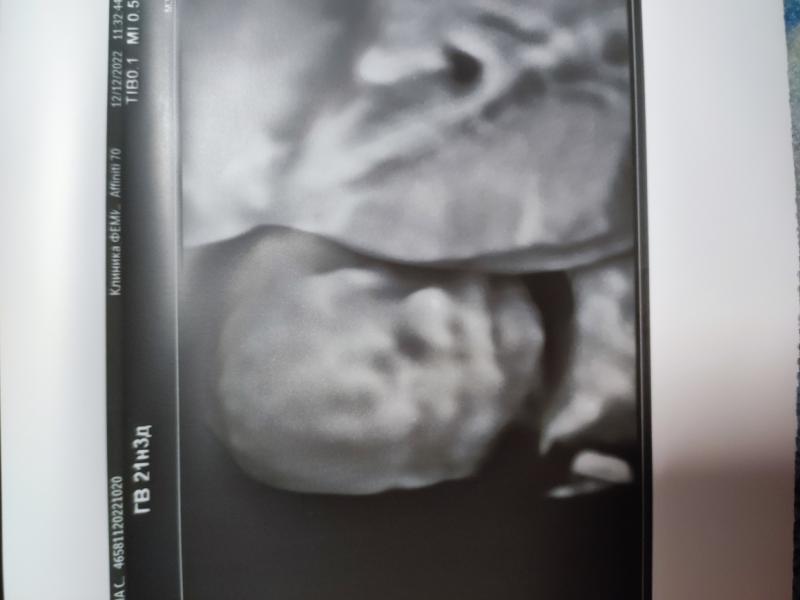

Сегодня был второй скрининг. Нам сказали что у нас будет ДОЧЬ! Муж счастлив.

По показателям все в норме) Счастью нет предела🤰🏼🥰🥰🥰

Скажите, а вот на снимке втором у Вас сбоку написано ГВ 21н3д. Это срок по первому скринингу или по месячным? Дело в том, что у меня тоже на день скрининга получается 20,4нед по месячным, а 21,4нед по первому скринингу.